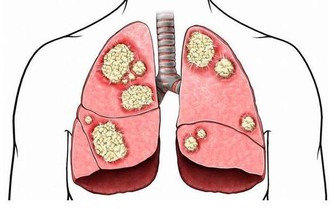

二、胸痛

對於女性來說,乳房的健康狀況一直受到她們的關注,因為乳腺癌是女性的噩夢。所以很多人對於胸部平時會出現的某些疼痛又或者是異樣,都會感覺到十分的恐懼。所以小編今天就來給大家簡單的介紹一下,胸部到底在出現哪些疼痛的時候,是需要我們所關注的。

比如說,有些女性在平時的生活中,胸部有時候會有莫名的脹痛,那麼在這樣的情況之下,就會造成一些女性的恐慌,這是不是代表自己出現了什麼樣的疾病。

其實,胸部有時候會疼痛,只是因為乳腺增生還有就是乳腺炎造成的,所以在這樣的情況之下,只要我們注意平時對它的保養,還有就是去醫院做檢查就可以很好的幫助你排除乳腺癌的風險。

因為早期的乳腺癌患者,她們平時病痛的發病率是比較小的,所以常常沒有什麼樣的疼痛感,直到最後晚期才會出現明顯的刺痛感,還有就是腫痛。這常常是因為乳腺增生,還有就是乳腺瘤壓制導管所造成的。

所以說,女性要想避免乳腺癌的發生,從現在注意就可以了。但是不能過分的在意,因為就像上文中小編說的那樣,有的時候,出現疼痛只是因為乳腺增生等造成的,只要平時注意按摩,還有就是做定期的健康檢查就可以了。

這裡所指的檢查有兩種,一種是進行自我的檢測,平時多關注一些,用手部感知它裡面有沒有出現腫塊等。一旦發現,立刻去醫院就診。還有就是要養成定期做體檢的習慣,因為這樣才全方位的保證你的健康。